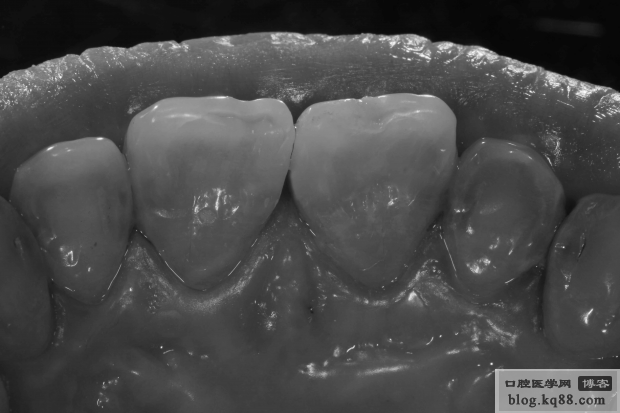

隔日修整初步拋光

隔日高光澤度拋光

隔日高光澤度拋光黑白照